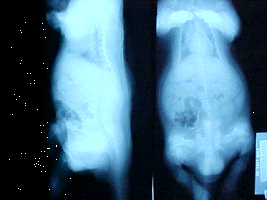

Pelvic X-ray of broken femur X-ray found that he had a broken pelvis, right about where the femur bone connects.

Treatment: This is what we used - Missing Link for felines, one Osteoform Chewable 150 CT crushed up, this is a calcium, phosphorus and vitamin supplement for dogs, one 500mg B-12 crushed up per day and mixed in a couple of large spoons of low fat yogurt. We give him the yogurt mixture before he gets his regular food, so we are sure he [eats] it. We have been doing this for several months. X-rays now show the bones fused back together.